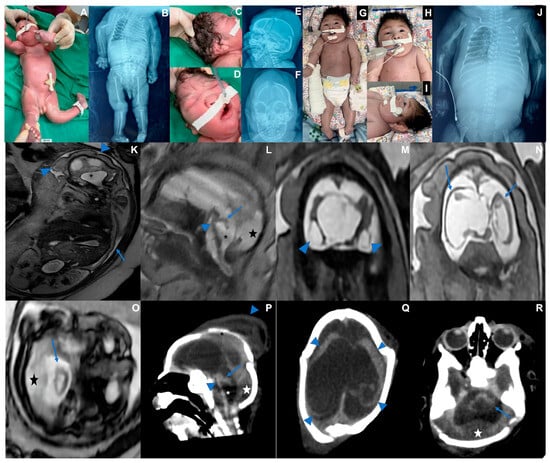

3.3. Case 3 (Figure 3)

| Microcephaly/Craniofacial disproportion/Skull collapse/short neck | Yes | Yes | Yes |

| Arthrogryposis multiplex | No | Yes | Yes |

| Fetal hydrops | No | Yes | Yes |

| Neurologic findings | Hypotonia, deep tendon hyperreflexia, dystonia, and epileptic seizures | Severe hypotonia (flaccid paralysis), no primitive or deep tendon reflexes, lack of suction, slow swallowing | Hypotonia, no deep tendon reflexes, lack of suction, slow swallowing |

| Ophthalmological findings | Visual impairment and nystagmus at 3 months | Corneal edema, optic disc atrophy, and chorioretinal scar in OU | Optic disc pallor and increased disc cupping (OS), chorioretinal macular scar and focal pigment mottling (OU), and vascular attenuation (OS) |

| Brain and Spinal Cord Images | Overlapping sutures, marked cerebral atrophy, partial lissencephaly, absent corpus callosum, brain cysts (cystic encephalomalacia and/or chronic subpial hemorrhages), subdural effusion, suspected striatal fusion, normal posterior fossa, normal spinal cord | Overlapping sutures, marked cerebral atrophy, absent corpus callosum, diffuse lissencephaly, severe brainstem and cerebellar hypoplasia, brain cysts (cystic encephalomalacia and/or chronic subpial hemorrhages), subdural effusion | Overlapping sutures, moderate cerebral atrophy, hypoplastic corpus callosum, diffuse lissencephaly, severe brainstem and cerebellar hypoplasia with Dandy–Walker-like features, intraventricular hemorrhage Global thinning of the spinal cord, mainly on the thoracic segment |